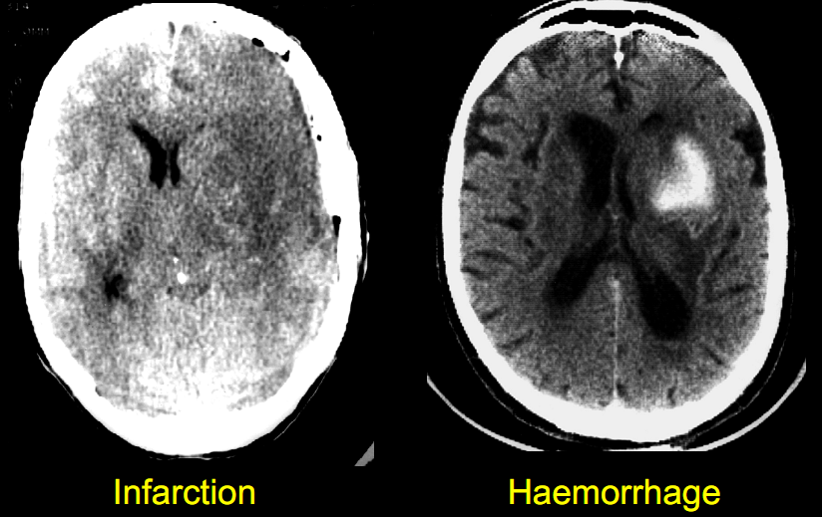

- Chẩn đoán loại tai biến: nhồi máu hay xuất huyết

Chẩn đoán loại tai biến

- Nhồi máu: 80% – 85%

- Xuất huyết: 15-20%

Chắc chắn nhờ xét nghiệm hình ảnh: CT

Chẩn đoán dễ dàng bằng CT